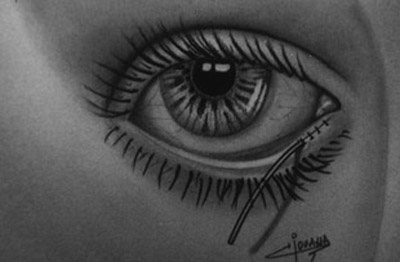

Bajo microscopio (a 16 aumentos) y con anestésia local, Xilocaina al 2% con adrenalina, inyectada sub dérmica en el tercio interno del parpado inferior, canto medio, procedemos a evertir un poco el borde palpebral inferior con un aplicador de algodón, para exponer el area marsupializada del canalículo, dejando la luz mucosa ampliamente expuesta.

Con un trozo de cuchilla de afeitar, montada en un portacuchillas Barraquer, se practican dos incisiones horizontales, a lo largo de la porción marsupializada del canalículo, para independizar los planos anatómicos, separando así los bordes interno o muco-mucoso y externo o muco-cutaneo.

Colocamos un elemento de interposición dentro de la luz canalicular, que puede ser una varilla de Veirs o un tubo de Silicona con un diametro de 1mm. Estos elementos sirven de molde para reconstrir sobre ellos la luz canalicular.

Se practica entonces una sutura muco- mucosa, uniendo los bordes internos con puntos separados de Nylon 10-00, dejando los cabos de sutura muy cortos, casi a ras del nudo, luego procedemos a poner puntos separados del mismo material para unir los bordes externos o muco-cutaneos, dejando los cabos de sutura de 2mm de largo para facilitar su remoción a los diez dias del período post operatorio.

El extremo externo del tubo se Silicona se fija a la piel del párpado inferior, con unos puntos separados de Nylon 10-00, sobrepasando el borde palpebral y descendiendo en piel 1cm. Observando que la cicatrización sea satisfactoria.